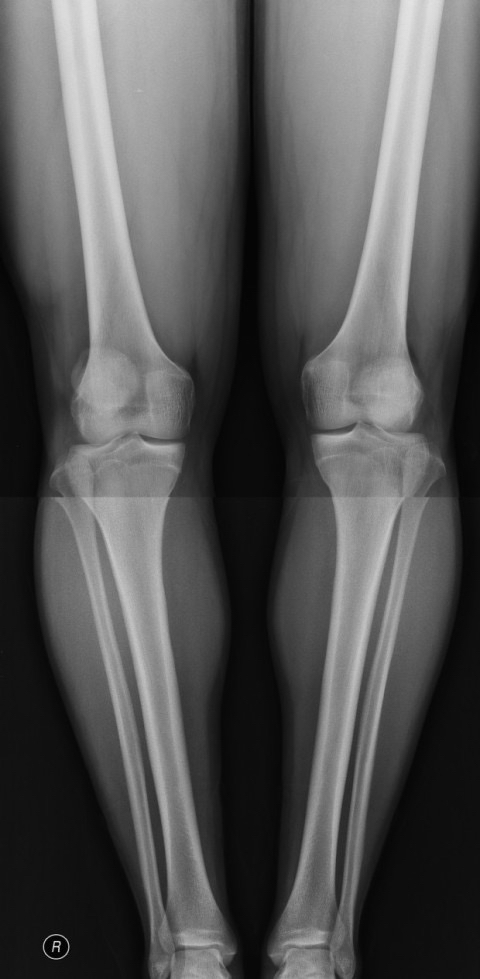

17세 엑스레이 사진 골연령과 성장판

위 사진은 17세때 찍은 엑스레이 사진인데 골연령하고 성장판 나이좀 알려주세요 ! 그리고 남자는 골연령 몇살까지 성장하나요 ??

무릎뼈사진으로 골연령을 측정하지는 않습니다. 손뼈를 찍어야합니다.

성장판은 아직 열려있는것 같네요.